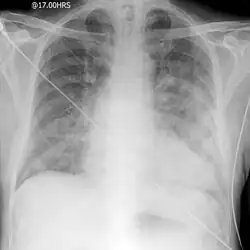

Negative-pressure pulmonary edema (NPPE), also known as Postobstructive Pulmonary Edema, is a clinical phenomenon that results from the generation of large negative pressures in the airways during attempted inspiration against some form of obstruction of the upper airways.[1][2][3] The most common reported cause of NPPE reported in adults is laryngospasm, while the most implicated causes in children are infectious croup and epiglottitis. The large negative pressures created in the airways by inhalation against an upper airway obstruction can lead to fluid being drawn from blood vessels supplying the lungs into the alveoli, causing pulmonary edema and impaired ability for oxygen exchange (hypoxemia).[4] The main treatment for NPPE is supportive care in an intensive care unit and can be fatal without intervention.[1][2]

NPPE develops as a result of significant negative pressure generated in the chest cavity by inspiration against an upper airway obstruction. These negative pressures in the chest lead to increase venous supply to the right side of the heart (preload) while simultaneously creating more resistance for the left side of the heart to supply blood to the rest of the body (afterload).[4] This large negative force also results in a decrease of the forces exerted by fluids outside of the pulmonary blood vessels. This results in an increased amount of fluid shifting from these vessels into the lower pressure extravascular space. While there normally is a net passage of fluid out of the vasculature at baseline, this is a small enough amount to be drained from the extravascular space by the lymphatic system, and as such fluid does not accumulate. In the setting of NPPE, the excess shift of fluid overcome the ability of the lymphatic system, and fluid (edema) accumulates in the alveoli of the lungs. As these structures are important for gas exchange during respiration, patients with NPPE struggle to have adequate oxygen supply to the tissues of their body.[1][4]